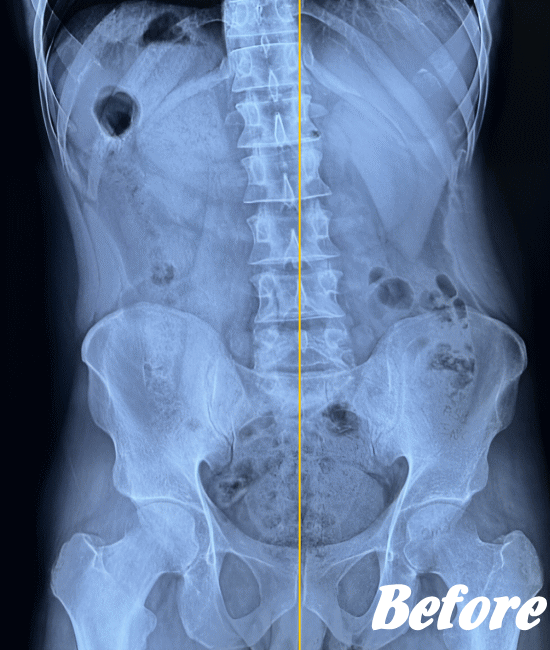

おそらく、ぎっくり腰を起こした状況や腰の状態から、筋肉や骨、椎間板、靭帯などのいずれかに障害が起きていると考えられるのですが、レントゲンなどの画像検査でも異常は認められないのです。

その中で、ぎっくり腰になった何人もの人の経緯を調べ、且つ、これまでの当院での施術経験からの一番の有力候補が、②の仙腸関節のズレであり、下図の「長後仙腸靭帯」に日常生活上のなんらかの動作により過大な負荷が加えられた結果、ぎっくり腰が発症するのではないかというものです。

実際、仙腸関節を調整しこの長後仙腸靭帯の緊張をリリースすると、著しい改善がみられています。ただし、あくまでヘルニアや狭窄などの他の腰の病気がない場合に限ります。